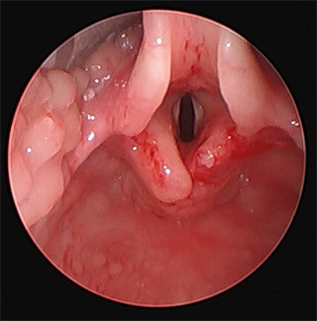

would increase the nasal cannula to 12 L/min and use a THRIVE technique. At this point, the surgical team used suspended direct rigid laryngoscopy and a CO2 laser to excise the excess arytenoid tissue in multiple steps: the resection of the excesses tissue was guided by the residual degree of prolapse after each excision (Figure 2).

Figure 2. Picture after partial laser supraglottoplasty.